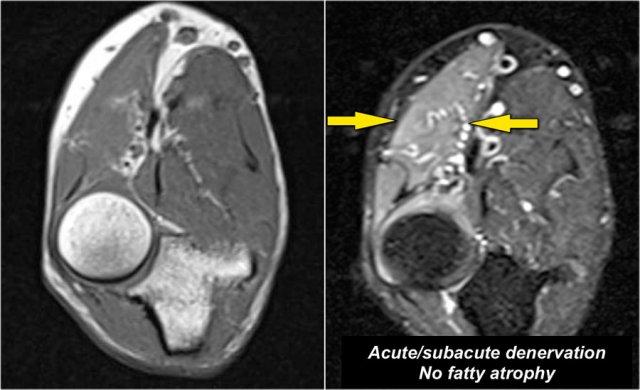

Đây là bệnh nhân nam 48 tuổi mắc hội chứng Marfan, khởi phát đột ngột yếu tay phải.

Đây là một ví dụ điển hình về mất phân bố thần kinh bán cấp.

Lưu ý trên ảnh T1W không có teo cơ.

Chỉ có phù nề trên ảnh T2W.

Nguyên nhân là do bệnh lý thần kinh quay đoạn gần.